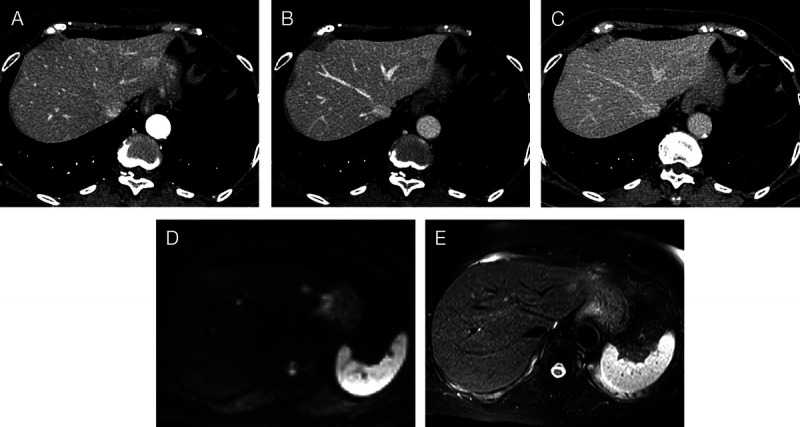

A suspected case of hepatic reactive lymphoid hyperplasia in which EUS-fine needle aspiration contributed to the diagnosis.

疑似肝反应性淋巴样增生病例,eus细针穿刺诊断。